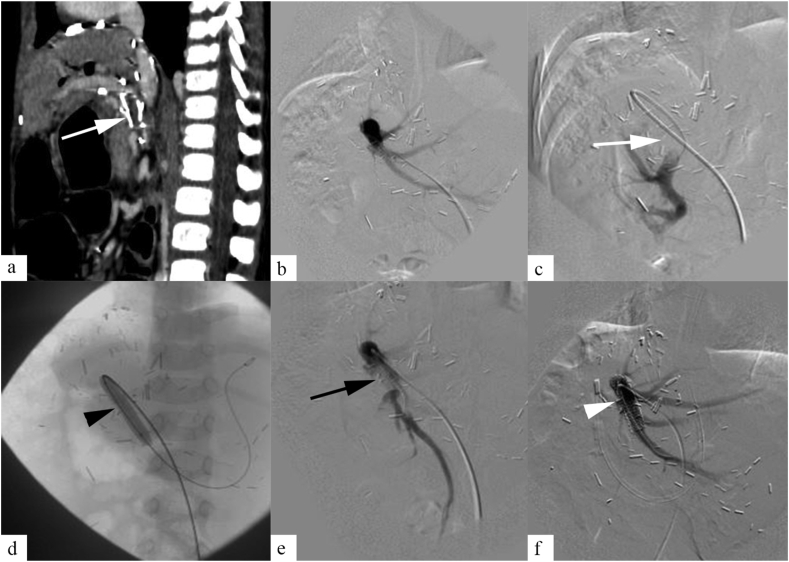

Figure 2.

A 34-month-old male child presenting with variceal bleeding, 3 months following liver transplantation. Contrast enhanced CT abdomen (a), and DSA (b, c) showed chronic thrombosis of portal vein graft (white arrow). Percutaneous transhepatic access was achieved, and balloon angioplasty was done for portal vein thrombosis (d, black arrowhead). DSA following angioplasty (e) showed residual portal vein thrombosis (black arrow). Stenting was done across the portal vein graft (f, white arrowhead), and final angiogram showed good flow across the stent.

Surgical revision is preferred in patients with early PVT occurring within 3 days of transplant. Retransplantation is considered in patients where surgical revision fails.13 In patients who are not suitable for surgery due to comorbidities, catheter-directed thrombolysis can be considered. Endovascular management is preferred in patients with PVT presenting between 3 days and 30 days posttransplant. Endovascular management includes catheter-directed thrombolysis, angioplasty, and/or stenting. In patients presenting after 30 days, management depends on clinical features. Asymptomatic patients with normal liver function are managed conservatively. Symptomatic patients can be managed with systemic anticoagulation and/or endovascular treatment (Figure 2).6